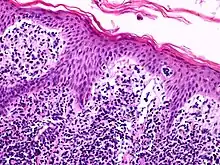

A histological view of Lutzner cells surrounded by erythrocytes in a blood smear.

Lutzner cells were discovered by Marvin A. Lutzner, Lucien-Marie Pautrier, and Albert Sézary. These cells are described as the smaller forms of Sézary cells, or Sézary-Lutzner[1] cells, and the two variants are recognised as being morphologically different. Aggregates of these cells in mycosis fungoides are known as a Pautrier's microabscesses. They are a form of T-lymphocytes that has been mutated[2] This atypical form of T-lymphocytes contains T-cell receptors on the surface and is found in both the dermis and epidermis layers of the skin. Since Lutzner cells are a mutated form of T-lymphocytes, they develop in bone marrow and are transported to the thymus is order to mature.[3] The production and maturation stages occur before the cell has developed a mutation. Lutzner cells can form cutaneous T-cell lymphoma, which is a form of skin cancer.[4]